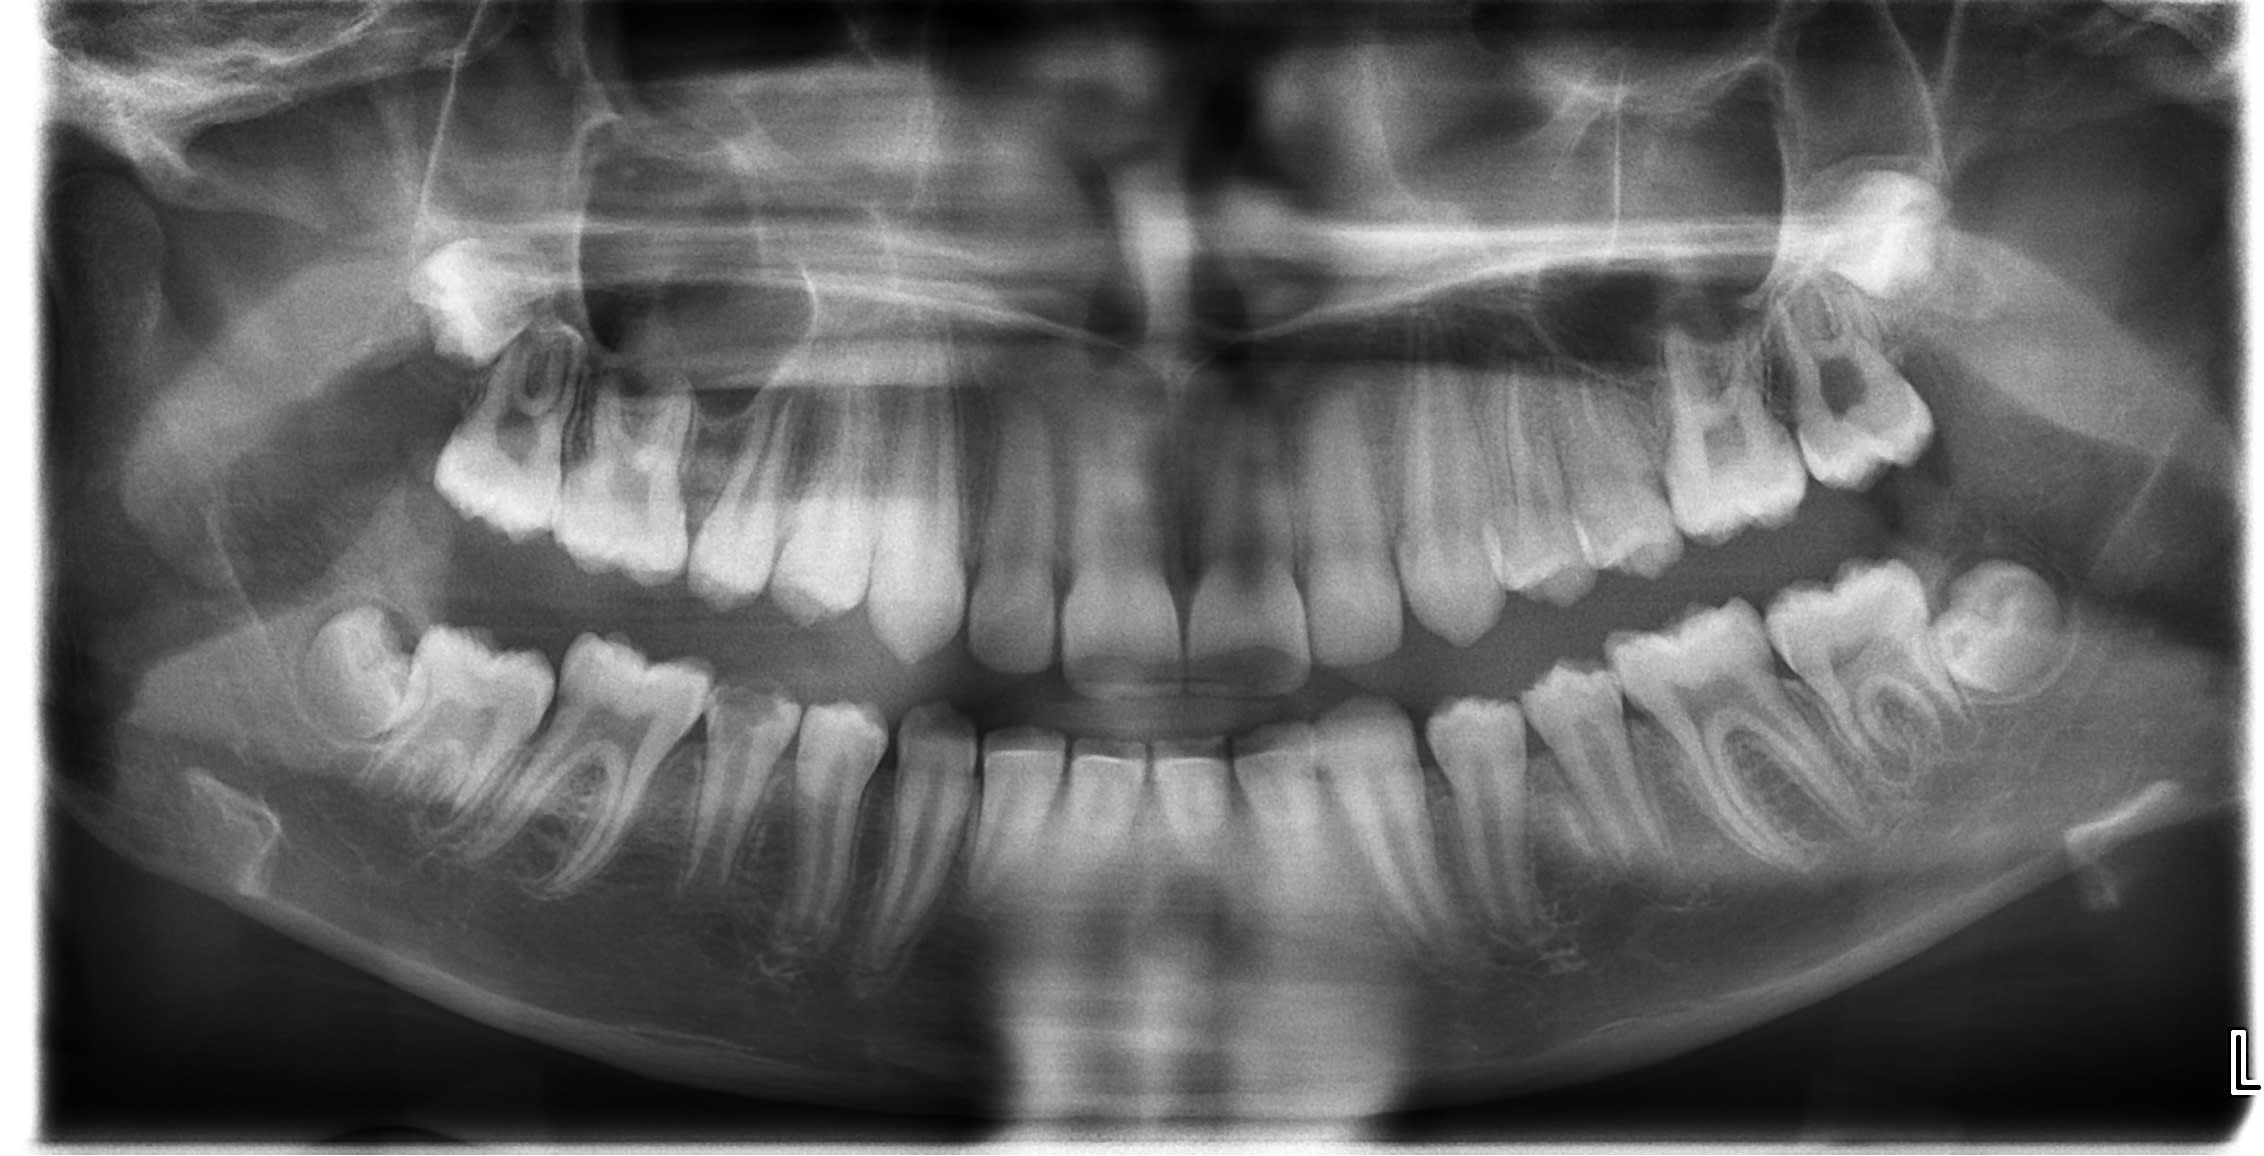

Je sollicite vos lumières pour ma jeune patiente de 11 ans en traitement orthodontique pour une classe 2.

L'hygiène bucco dentaire est correcte. Chez le grand frère il y a une agénésie de 14/24/25 et chez la grande soeur agénésie de 14/24/45.

A l'éruption,la couronne de 45 est constituée de son émail,sauf sur la face occlusale qui laisse apparaitre du "tissu conjonctif dentinaire" non minéralisé.

Il n'y a aucun symptomatologie

A la radio panoramique,la racine de 45 semble s'édifier normalement.

Pour ma culture générale, comment peut qualifier cette anomalie ?

- est ce que cette 45 est raisonnablement conservable ? (pronostic à moyen terme réservé je pense)

- si avulsion profite- t- on du traitement orthodontique pour:

1- fermer l'espace entre 46 et 44

2- maintenir l'espace entre 46 et 44 en vue de la pose d'implant vers 18/20 ans?